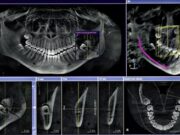

Компьютерная томография челюсти: современный метод неинвазивной диагностики

Все больше стоматологий предлагают своим пациентам пройти компьютерную томографию. Метод основан на рентгеновском излучении. Разная реакция рентгеновских лучей на анатомические структуры тела, позволяет увидеть...